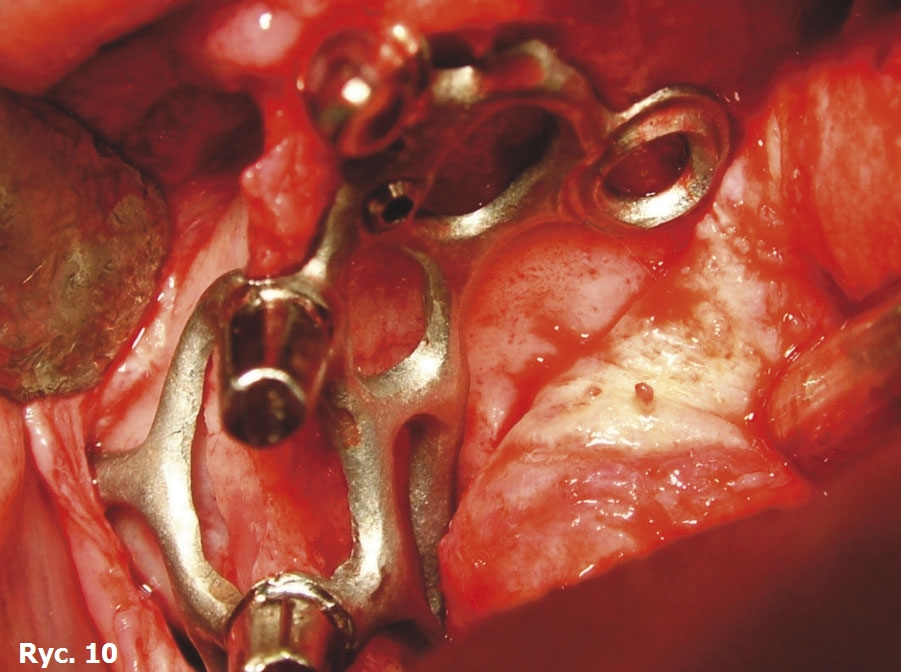

Wyniki badania TK oraz model stereolitograficzny pozwoliły na wykonanie dwóch oddzielnych siatek wszczepu podokostnowego w obrębie łuku górnego (ryc. 9), które zostały później wszczepione (ryc. 10) oraz połączone ze sobą, aby wspólnie przenosić siły żucia (ryc. 11), stanowiąc podparcie dla estetycznego uzupełnienia protetycznego stałego (ryc. 12, 13). Zabieg chirurgiczny przebiegł bez powikłań. Przysłana z Karaibów kartka pocztowa z trzema słowami „drugi miesiąc miodowy” potwierdziła, że cała wykonana przez lekarza praca zakończyła się sukcesem.